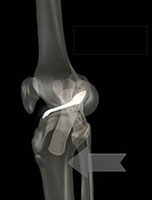

A cirurgia de reconstrução do ligamento cruzado anterior é realizada com auxílio de câmera de vídeo (denominada artroscopia) sendo realizada por pequenas incisões.

Na cirurgia, uma incisão é realizada para retirada dos enxertos e dois pequenos furos (pequenas incisões) para utilização das câmeras e dos equipamentos de vídeo. Uma outra pequena incisão pode ser necessária para fixação do novo ligamento junto ao fêmur (osso da coxa).